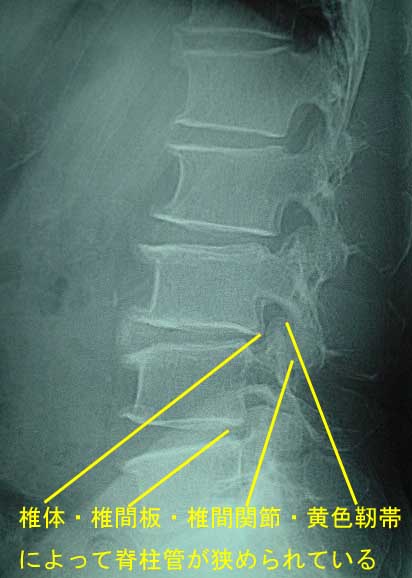

| 腰部脊柱管狭窄症 原因 腰部脊柱管狭窄症 とは脊柱管が加齢的な変化(腰椎症性変化)、すなわち椎体変形・椎間板変性・椎間関節変形・靭帯肥厚や骨化などによって脊椎管が狭窄(狭められ)て脊柱管内に存在する馬尾や腰神経が圧迫されて起こる疾患です。ちょうど、広いマンションで快適な生活を送っている方が、家具などの調度品が増えてくると、部屋(脊椎管)が狭くなり圧迫感や不快に感じるのと似ております。 症状 腰痛やお尻の痛み、足先に放散する痛み、シビレなどを訴えます。特徴的な症状として間欠性跛行を認めます(数10m〜数100m程度歩くと、症状が増悪し休憩が必要となります)。 間欠性跛行には神経性のものと血管性のものがあります。神経性の腰部脊柱管狭窄症の跛行は、しゃがむと症状は改善されます(腰を丸めることにより神経の圧迫が軽減されるからです)。血管性の閉塞性動脈硬化症の跛行は、立ち止まっただけで症状は改善します(歩行を中止することにより下肢の血行が改善されるからです)。鑑別(見極め)は問診で容易です。 診断 診断は問診や診察所見で容易です。レントゲンでは脊椎管の狭小(これは正常な腰椎です)を認めます。詳細な情報収集にはMRI(正常な馬尾神経)、CT、脊髄造影、神経根造影などの検査が必要です。 治療 1)保存的治療 日常生活動作時の姿勢や睡眠時の姿勢などの指導をします。症例によってはダーメンコルセットや半硬性コルセットを着用をすすめます。コルセットは神経の圧迫を軽減するために軽度前屈位(前かがみの状態)で作成します。 疼痛緩和に物理療法(腰椎牽引療法など)やアセトアミノフェンを処方し、炎症緩和に非ステロイド性抗炎症剤や外皮用薬、ビタミンB12製剤、神経障害性疼痛薬、トラマドール塩酸塩、デュロキセチンなどを投与します。また、神経ブロック療法としてトイガーポイントブロックや腰部や仙骨部硬膜外ブロック、神経根ブロックなどを検討します。 治療目的や再発予防に腰のストレッチングや腰の筋力強化訓練、股のストレッチング、股の筋力強化訓練などの運動療法を指示します。なお、高齢者の腰部脊柱管狭窄症は、将来、ロコモに進展することがありますので注意深く観察し、症例によっては運動器リハビリテーションを指示します。 2)手術的治療 保存的治療で改善されない症例は手術が検討されます。術式は、病態が馬尾神経由来か腰神経由来かにより異なります。病巣部除圧術や骨形成的椎弓切除術や除圧術+椎体固定術などが検討されます。